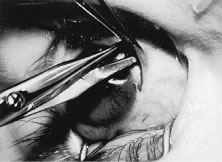

RECESSION PROCEDURE: FORNIX INCISION

This procedure is recession of the right medial rectus muscle. The eyelids are separated with a Barraquer open-blade wire eyelid speculum (Fig. 8). The open-blade design provides more room for exposure and makes it easier to pass the suture needles, especially in small children or when large recessions are performed. The globe is grasped with a Lester forceps at the limbus. It is best to grasp the limbus with the forceps held perpendicular to the globe and then to position the forceps so that they are rotated and lie tangential to the globe. Forced ductions are performed to detect any restriction of movement of the globe (Fig. 9).

Fig. 8. The lids are separated with a Barraquer open-blade wire speculum. The eye is abducted to test for restriction.

Fig. 9. A Lester forceps grasps the limbal conjunctiva to perform a forced duction test. Care is taken not to allow the globe to move posterior during this maneuver. Restriction of globe rotation should be recorded, and, if it is significant, adjustments in the surgical procedure may be considered.

The globe then is gently elevated from the orbit or proptosed at the same time it is abducted or adducted to prepare for the incision. Elevation of the globe helps to separate the horizontal rectus muscle from the inferior rectus muscle so that the inferior rectus muscle is not cut when the incisions are made. The conjunctiva is grasped by the assistant with a Manhattan toothed forceps (Fig. 10). This forceps has teeth that are angled outward and are designed to grasp conjunctiva, as well as the deeper subconjunctival tissue, so that when the blunt-tipped Westcott scissors cuts into the tented tissue, an incision is made into the conjunctiva and Tenon's capsule (Fig. 11A and B). If the incision does not completely penetrate Tenon's capsule and the intermuscular septum to the scleral surface of the eye, additional tissue (anterior Tenon's tissue and/or intermuscular septum) is grasped with the Manhattan forceps and at least one additional cut is made.

Fig. 10. The conjunctiva is tented between two forceps.

Fig. 11. A. A blunt-tipped Westcott scissors, held perpendicular to the globe, is used to make an incision through the conjunctiva, Tenon's tissue, and intermuscular septum. B. In this view, the surgeon is spreading the scissor blades and viewing bare sclera.